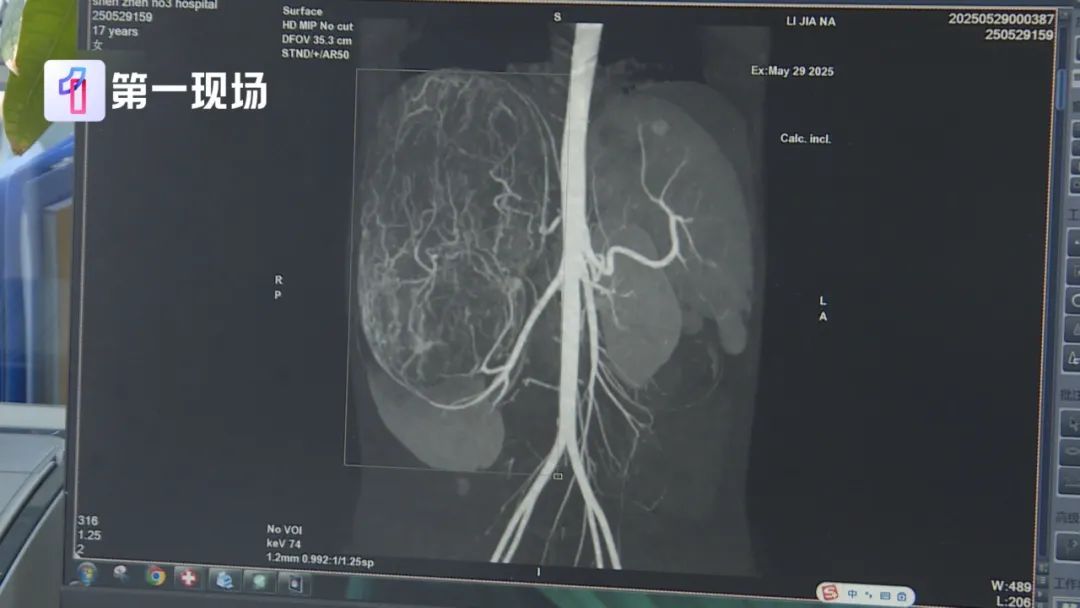

婷婷的肚子里

竟然长了一个巨大的肿瘤

肿瘤直径长达27厘米

等到了当地医院一检查,CT结果显示,她的右肾有恶性肿瘤伴肝转移可能,家长就立即带着孩子来到深圳求医。

我们发现肿瘤已经到了肚脐的下缘,就是后腹直肌外侧,这种情况用腹腔镜微创做不现实,安全地把肿瘤切除,不要把肿瘤搞破,是我们首先要考虑的问题。

送医后,医生表示婷婷的情况不能等,必须及时将肿瘤切除。但肿瘤体积过大,几乎占据了整个腹腔,周边器官也被严重挤压,留给医生的手术空间实在有限。

肿瘤切出来后,我们测量了大小有27公分,重量有2.435公斤,非常非常的大,切得非常完整。